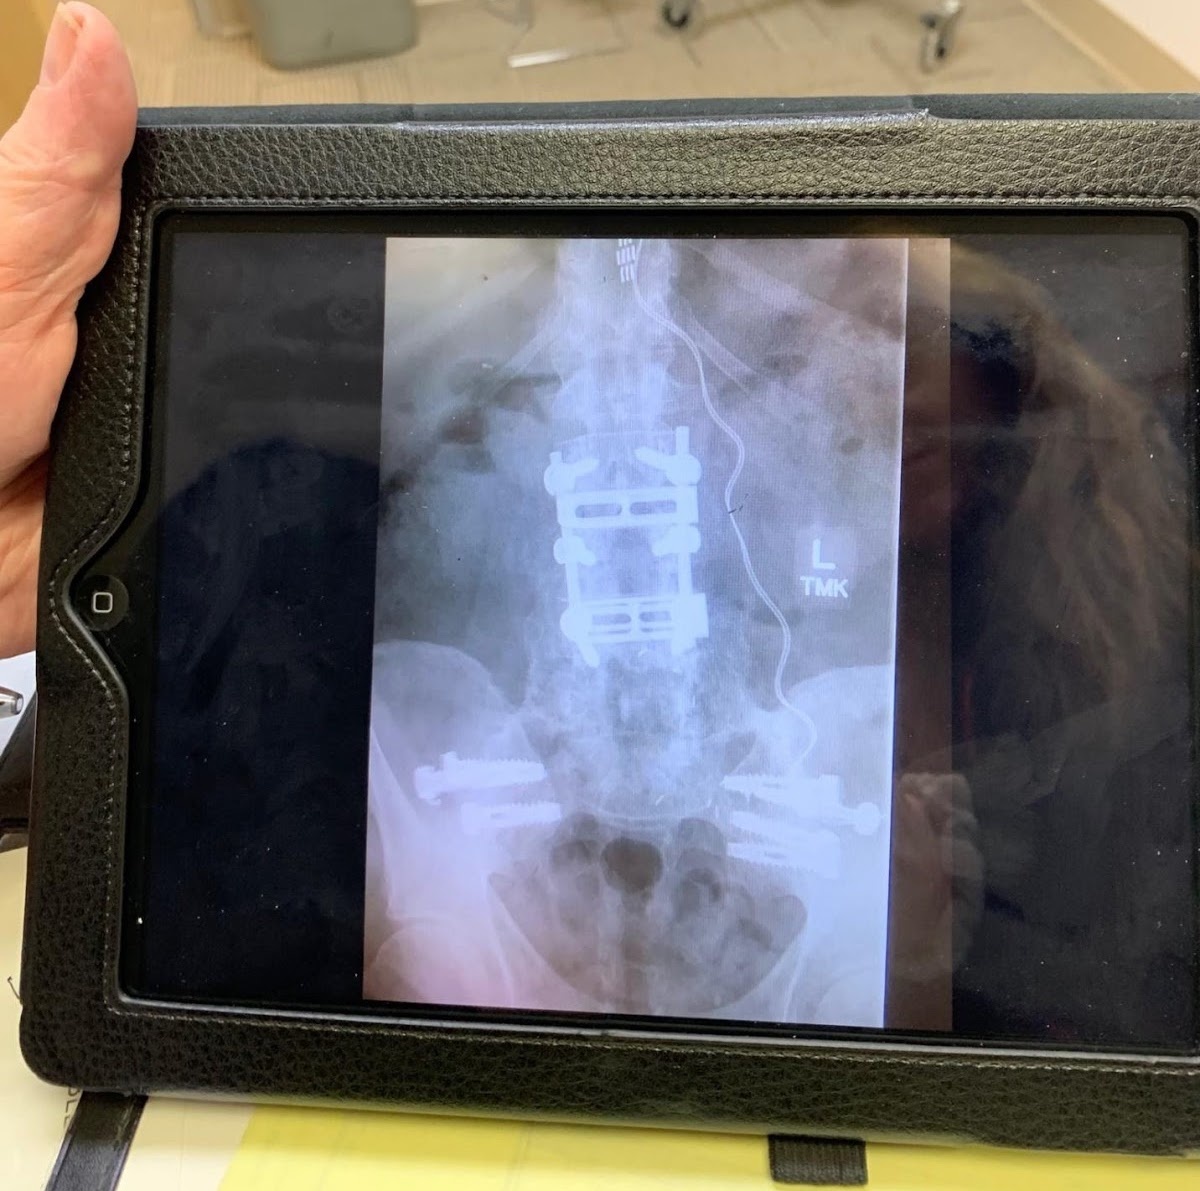

Cathartic. Therapeutic. Had anyone told me I would be writing; I would have called them nuts. This started out to be a chronological document so a shrink and I could sort through my trauma closet and start working on my nightmares and PTSD. That turned into “The Observing Ego” template and I hit my stride and was able to start working on my issues. I came home with a rage syndrome that scared the hell out of people. Combined with my “adrenaline seeking behaviors,” I was socially unacceptable and targeted routinely by Law Enforcement as a possible “ax murderer.” And I loved it. It kept people away from me. I didn’t have to talk to anyone. I self-isolated, and was taking way too many narcotics and other meds from the VA. After 39 spinal reconstructions and surgery to repair my body from a T.O.W. missile strike, “Friendly Fire,” I found myself climbing back out of the crab bucket, living in a wheelchair as a homeless veteran in a park in N.C. to coming to California to see a Dr. G in Daly City who eventually got me out of the chair, surgically implanted a “Dorsal Column Stimulator” in my spinal cord, fused my pelvis and spine finally the correct way and turned my life around.

Photos of the surgery completed on Kuryla’s back. Photo credit Kuryla.